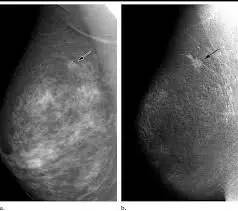

★ 乳腺钼靶(X光)检查:乳腺钼靶检查其实就乳腺X光检查,把整个乳房压扁利用X光透视乳房的内部情况,能够发现乳腺癌的早期症状。

由于年轻女性的乳房腺体比较多,发生病变的组织容易和腺体重叠,分不清楚究竟是病变还是正常的腺体。因此,40岁以下女性一般不做乳腺钼靶检查。

图:乳腺钼靶检查发现乳房细小的病变